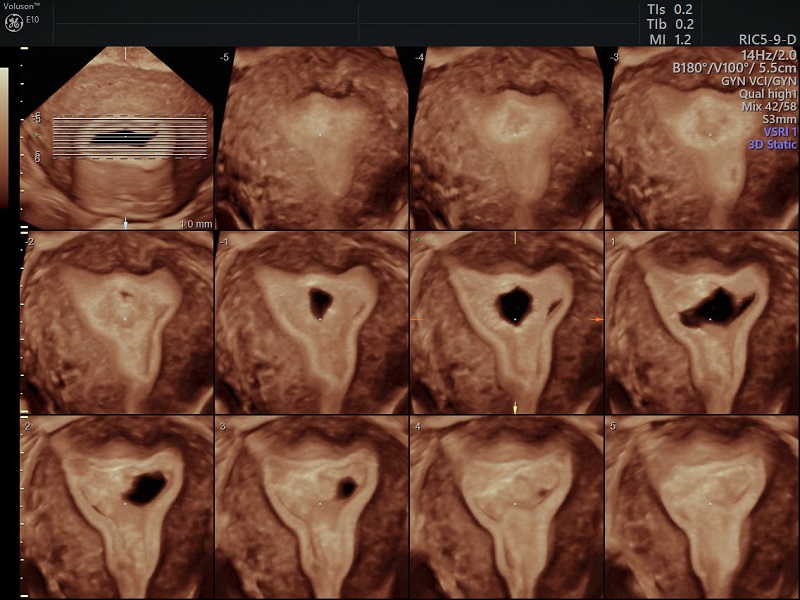

همانند سونوگرافی دوبعدی (2D USG)، در معاینه زنان و زایمان با USG سه بعدی، روش ترانس واژینال ارجحیت دارد. مبدل همچنان نزدیک به ناحیه مورد نظر نگه داشته می شود و یک جستجوی سریع در زاویه مورد نظر انجام می شود. داده های به دست آمده برای به دست آوردن حجم استفاده می شود. داده های ذخیره شده الکترونیکی برای نمایش سه صفحه متعامد پردازش می شوند. این تجهیزات را می توان به دلخواه چرخاند یا جابجا کرد و می توان آنها را با هم متحد کرد تا یک تصویر سه بعدی را تشکیل دهد. دستکاری داده های حجم به دست آمده برای بررسی یک ساختار خاص، مانند رندر سطح برای ارزیابی ناهنجاری های مادرزادی رحم امکان پذیر است. گزینه دیگر این است که حجم را به صورت برش مشاهده کنید، مانند توموگرافی کامپیوتری. به این تصویربرداری چند برشی می گویند. تعداد برش ها و فضای بین آنها توسط کاربر تعریف می شود.

یکی از ویژگی های برجسته 3D USG توانایی آن برای به دست آوردن تصاویر در تجهیزاتی که قبلاً در دسترس نبودند با استفاده از 2D USG است. Coronal plane می تواند اطلاعات دقیقی در مورد رحم و آدنکس ارائه دهد و به ویژه در تشخیص ناهنجاری های مادرزادی رحم مفید است (شکل 1). به همین ترتیب، کف لگن را می توان به طور موثر در سطح محوری با استفاده از USG سه بعدی ارزیابی کرد. علاوه بر این، کاربر توسط این هواپیماهای معمولی محدود نمی شود. ساختن هر صفحه ای از داده های حجم به دست آمده امکان پذیر است.

در سال های اخیر ثابت شده است که 3D USG یک ابزار بسیار قدرتمند برای تشخیص ناهنجاری های رحمی است. مهمترین مزیت USG سه بعدی برای تشخیص ناهنجاری های رحمی، توانایی آن در به دست آوردن نمای تاجی از رحم است که در USG دو بعدی به دلیل وجود لگن استخوانی امکان پذیر نیست. این نما به وضوح خطوط خارجی رحم را مشخص می کند و همچنین اطلاعات دقیقی در مورد شکل حفره ارائه می دهد. در حالت ایده آل، ضخامت آندومتر در طول معاینه باید حداقل 5 میلی متر باشد، زیرا مزایای نمای 3 بعدی تاج در اندومتر نازک تر به میزان قابل توجهی کاهش می یابد

اخیراً استفاده از USG سه بعدی در ترکیب با SIS مورد بررسی قرار گرفته است. لودوین و همکاران در مطالعه خود روی 117 بیمار. 3D SIS، 3D USG، و 2D USG را مقایسه کرد. 3D SIS دارای دقت، حساسیت و ویژگی 100 درصدی بود و در تشخیص ناهنجاری های رحمی به طور قابل توجهی بهتر از بقیه بود. این تنها روشی بود که 100% با یافته های هیستروسکوپی و لاپاراسکوپی مطابقت داشت . یکی دیگر از مزایای 3D SIS این است که نیازی به ضخامت آندومتر از 5 میلی متر ندارد. در مطالعه دیگری بر روی 141 بیمار، SIS سه بعدی نیز 97.2 درصد برای ارزیابی کلی شکل حفره رحم، شکاف فوندال و چسبندگی های داخل رحمی حساسیت دارد. با توجه به این نتایج، نیاز به هیستروسکوپی با نگاه دوم تقریباً برطرف شده است

چسبندگی داخل رحمی یکی از علل شناخته شده ناباروری است. HSG و 2D SIS دو روش رایج برای تشخیص آن هستند، در حالی که هیسترئوسکوپی استاندارد طلایی است. نقش 3D USG در تشخیص به طور گسترده مورد بررسی قرار نگرفته است. یک مطالعه با مقایسه 3D USG و HSG گزارش داد که 3D USG دارای حساسیت 100٪ و HSG 66.7٪ برای تشخیص صحیح و درجه بندی چسبندگی های داخل رحمی است. HSG عمدتاً در تشخیص چسبندگی بخش تحتانی رحم شکست خورد و آنها را با انسداد کامل حفره اشتباه گرفت . احمدی تصدیق کرد که SIS سه بعدی ابزاری مفید و کم تهاجمی است.